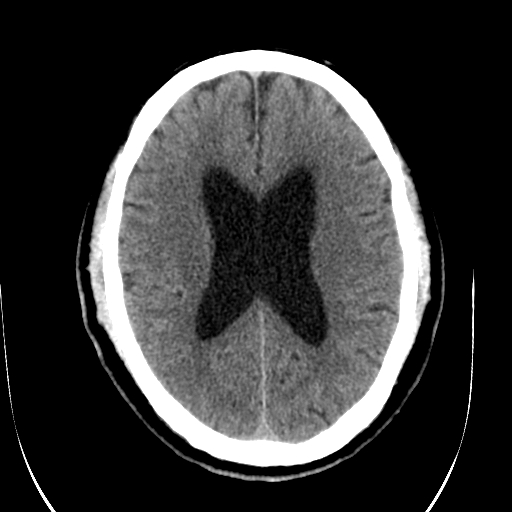

标题: CT28335:男,58岁,请各位看看是不是有脑积水,蝶窦内高密 [打印本页]

标题: CT28335:男,58岁,请各位看看是不是有脑积水,蝶窦内高密

轻度积水,蝶窦正常。

脑积水!建议行mri!

1)脑积水。2)副鼻窦炎。